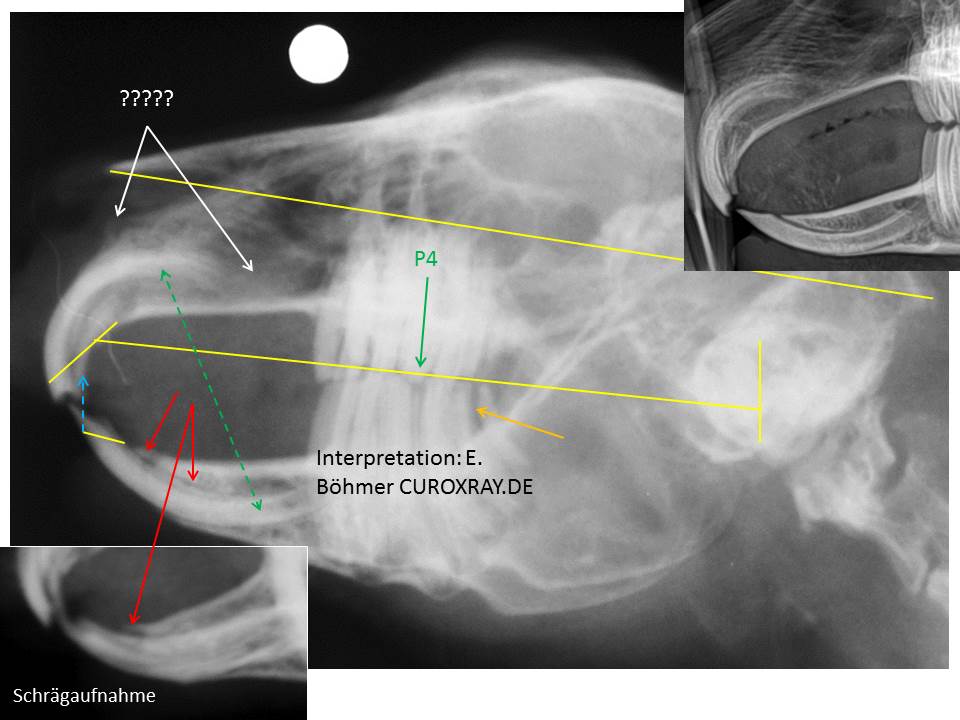

Dieses Kaninchen leidet meines Erachtens an einer chronischen Entzündung der oberen Atemwege. Im Bereich der Choanen ist kalzifizierter Eiter zu sehen (siehe später mehr dazu) und durch eine vermutlich aufsteigende Infektion via Tuba Eustachii sind beide Mittelohren betroffen (einseitige Verdichtung der Bulla tympanica (gestrichelter gelber Pfeil) und contralateral fast vollständige Lyse der Wand des Mittelohres (gelbe Pfeile).

Bei diesem Patienten ist darüberhinaus auch der Tränen-Nasenkanal verdichtet (rechte weiße Linien) und das Lungenfeld infolge der chronischen Rhinitis leicht überbläht (Emphysem) (Bild des Thorax hier nicht enthalten). Die seitliche Röntgenaufnahme des Kopfes lässt im Bereich überhalb der Mitte der oberen Schneidezähne eine eigenartige Struktur erkennen (????), die mir so nicht bekannt ist. Da in diesem Bereich der Tränen-Nasenkanal in die Nasenhöhle mündet, sollte man sich diesen Bereich klinisch nochmals genauer anschauen und den Tränen-Nasenkanal auch unbedingt spülen. Auch Kontrastmittelstudien wären möglich. Hinzu kommt, dass die klinischen Kronen der Schneidezähne im Ober- und Unterkiefer deutlich zu lang sind (kurze gelbe Linien) und die extrem spitz auslaufenden unteren Inzisivi unphysiologisch mit ihren maxillären Antagonisten okkludieren = direkter Kontakt und pathologischer Okklusionsfläche (blauer gestrichelter Pfeil). Die normale Situation zeigt das Bild rechts oben. Im Bereich der unteren Inzisivi ist kaudal der sichtbaren Zahnkrone eine Knochenlyse erkennbar (roter Pfeil) (seitliche Aufnahme und Schrägaufnahme). Dem sollte man ebenfalls nachgehen (periodontale Infektion? Symphyse noch intakt? Einseitig? Folge des häufigen Einsatzes von Kiefersperrern?). Im Vergleich zu den oberen Prä-Molaren sowie Molaren sind die unteren Backenzähne intraoral zu lang und die gesamte Kaufläche der Backenzähne ist sehr uneben (untere lange gelbe Linie). Der dritte Oberkieferbackenzahn (P4) drückt sich in einen entsprechend erweiterten Approximalbereich im Unterkiefers (vermutlich P4-M1 –Seite?) (grüner Pfeil). Dies erfordert ebenfalls eine weitere Diagnostik (intraorale Aufnahmen), da sich hier immer wieder Futterpartikel einspießen können, die sich dann zersetzen und so progressiv eine lokale periodontale Entzündung verursachen, die unaufhaltsam weiter fortschreitet. Darüberhinaus bedarf der erweiterte Approximalbereich zwischen den beiden letzten unteren Backenzähnen (M2-M3 Seite?) ebenfalls einer weiteren diagnostischen Abklärung (orangener Pfeil).

Mir erscheint auf der dv-Aufnahme der linke Bulbus weiter aus der Orbita herauszustehen als dies rechts der Fall ist (gelbe Linien). Dies könnte die Folge der schwerwiegenden linksseitigen Otitis media sein, die mit einer deutlichen Knochenlyse einhergeht (sekundäre retrobulbäre Entzündung bzw. Schwellung). Auch dies sollte weiter abgeklärt werden (klinische Diagnostik und ev. Ultraschall). Wie bereits zu Beginn dieser Diskussion erwähnt, zeigt das dorsoventrale Röntgenbild im Bereich der Choanen mehrere kleine röntgendichte Strukturen (roter Pfeil), die mit kalzifiziertem Eiter vereinbar sind. Zum Vergleich links oben der entsprechende Bereich bei einem gesunden Kaninchen. Der Bereich der Choanen ist frei und gut belüftet (gestrichelter roter Doppelpfeil).